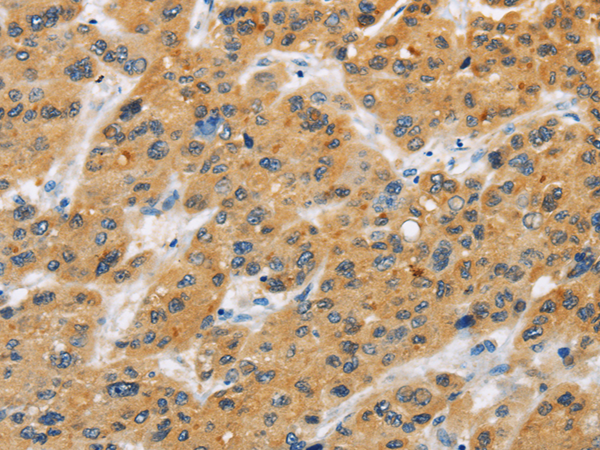

分类: 科研抗体货号: P08108别名:应用: WB,IHC反应种属: Human, Mouse, Rat